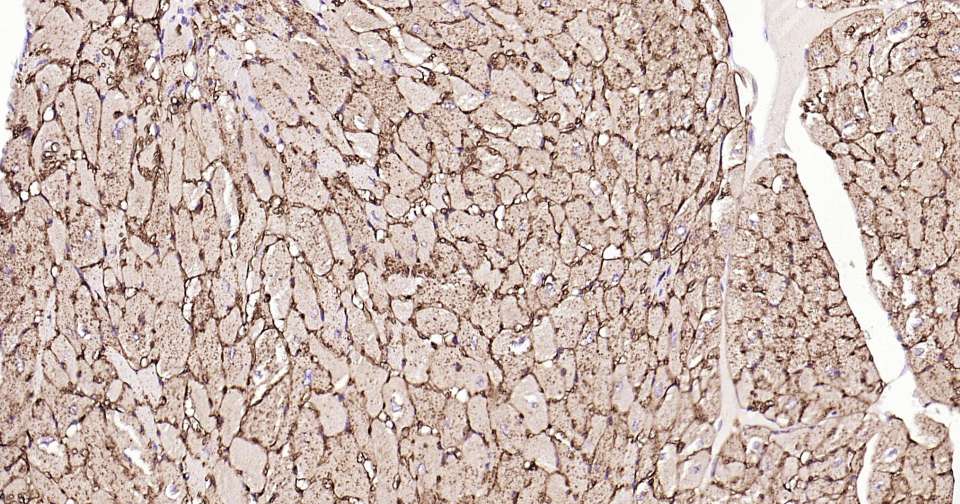

Immunohistochemical analysis of paraffin embedded mouse heart tissue slide using IHC0331M (Mouse CD36 Kit).